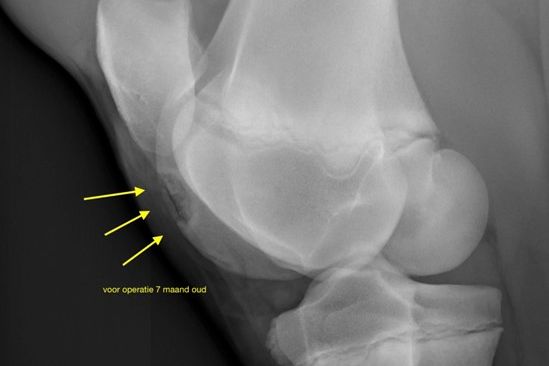

Zeven maand oud veulen met groot OCD letsel in de knie voor de operatie.

Het veulen van de fokker heeft zichtbaar een opgezette knie. De radiografie wijst duidelijk op een beginnende OCD. Het bot is nog niet helemaal los en nog niet gemineraliseerd, of verbeend. Er zit dus nog geen kalkaanslag op, maar je ziet wat er aan het gebeuren is. Dit is het begin van OCD.

Tientallen jonge paarden ondergaan vol ongeduld hun eerste fotoshoot. Onderweg naar de volgende klant belt een fokker omdat zijn veulen van zeven maanden achteraan mankt. Een juiste diagnose kan gesteld worden door radiografie van de knie. Uit ervaring weet Frederik Mijten dat kreupelheid achteraan kan wijzen op osteochondrose van de knie.